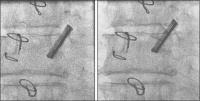

Durchleuchtung Projektion

Abbildung 9: Durchleuchtung RAO 10°, Seitenansicht der Prothese: eindeutig freies Klappenspiel.

Keywords: KardiologieKlappenspielProjektion